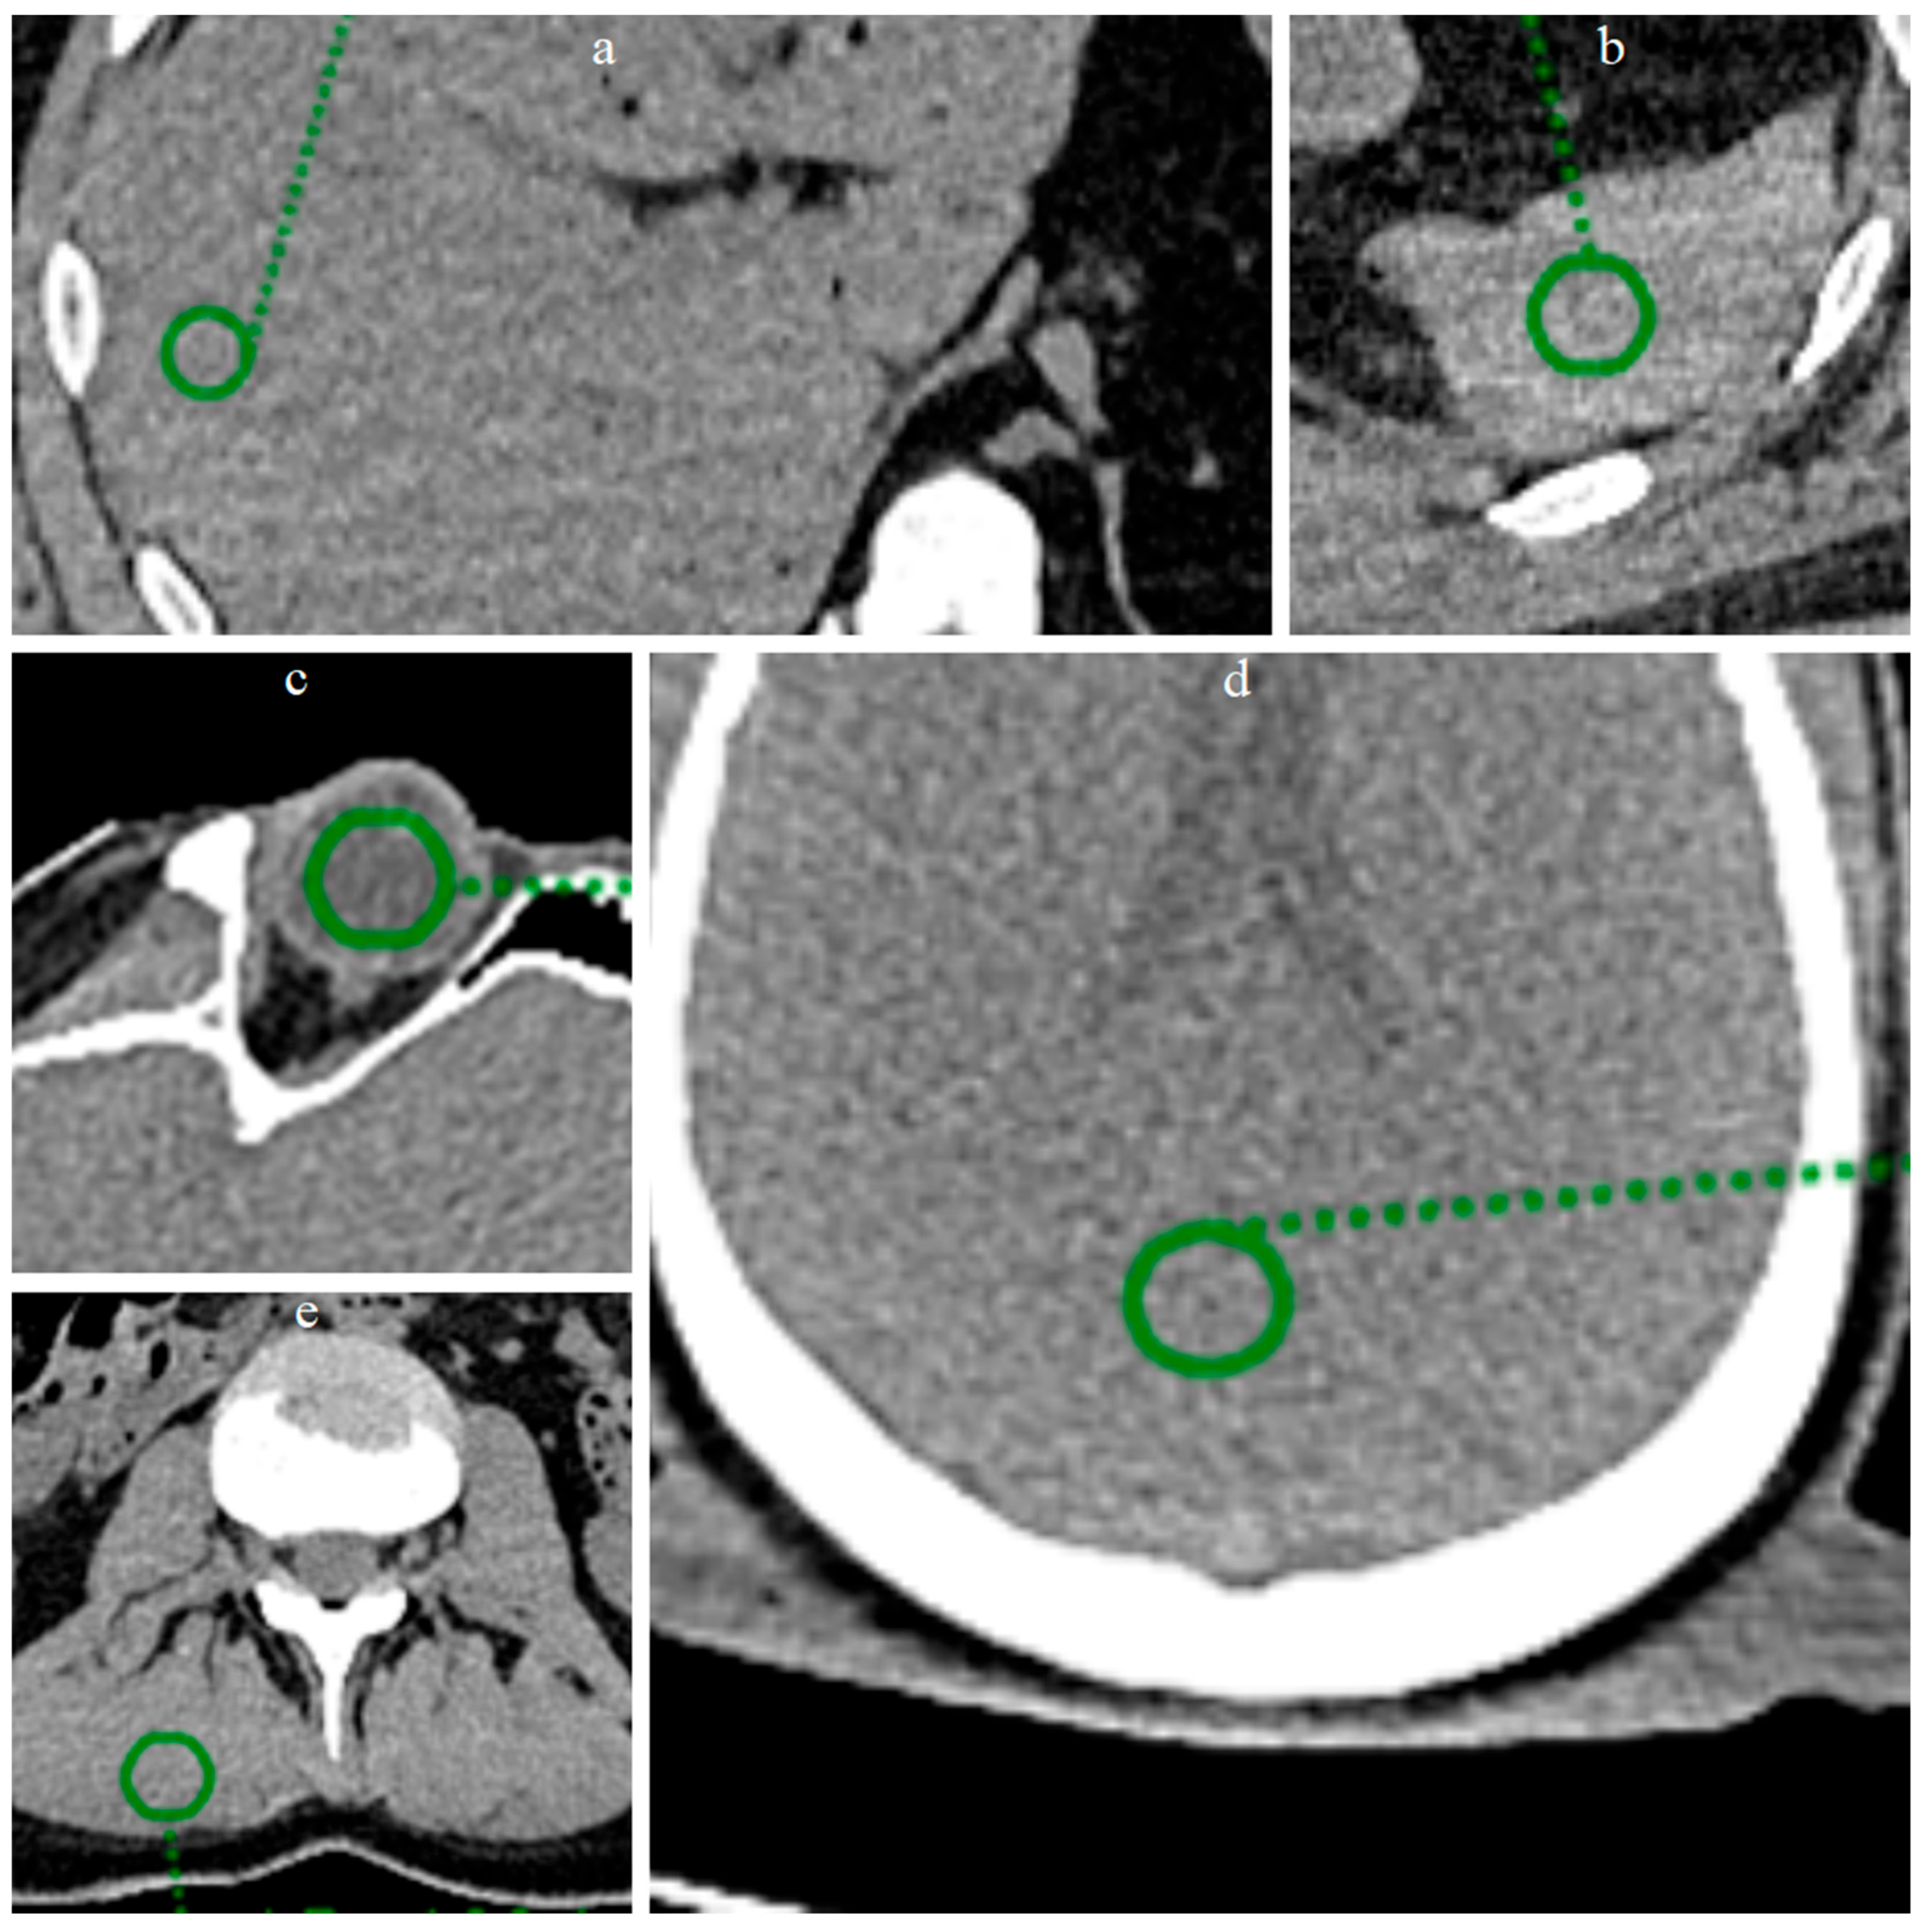

3.2. ROI Results

| Organ | Mean HU | SD | Difference HU (%) |

|---|---|---|---|

| Vitreous LQ | 18.75 | 17.60 | 7.95 |

| Vitreous ErisNet | 18.00 | 16.20 | |

| Brain LQ | 45.50 | 18.85 | 18.30 |

| Brain ErisNet | 46.00 | 15.40 | |

| Liver LQ | 59.00 | 19.65 | 13.36 |

| Liver ErisNet | 58.00 | 17.03 | |

| Spleen LQ | 54.61 | 25.11 | 12.01 |

| Spleen ErisNet | 52.34 | 22.09 | |

| Muscle LQ | 52.12 | 25.65 | 9.35 |

| Muscle ErisNet | 50.74 | 23.26 |